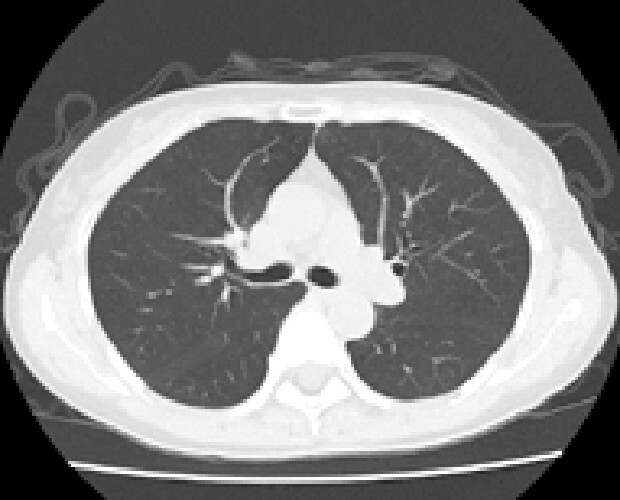

マルチスライスCTスキャナは寝台に横になるだけで頭部・胸部・腹部など体内を断層(輪切り)で撮影できる検査です。

従来装置(64列)に比べて高速、高精度の撮影が可能なだけでなく、患者様の体型に合わせて線量を可変できるため適切なX線量で検査できます。

診断や治療のために骨や血管の3D(立体的な三次元画像)を作成することもできます。